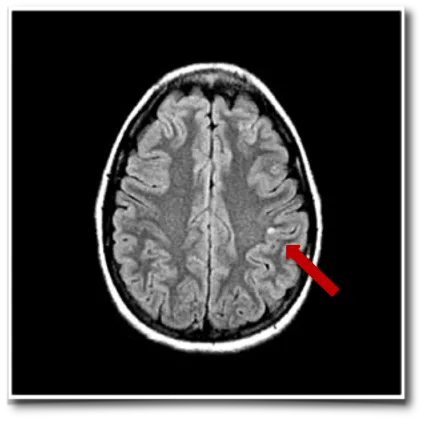

要想精准治疗癫痫,鲁特卡教授认为首先需要在术前进行精确的评估,而教授常用的术前评估技术包括磁共振成像(MRI)及脑磁图(MEG)。

琳娜的MRI检查结果显示,在她的顶叶存在一个小的囊性病变,而这正是导致琳娜癫痫频发的病灶。